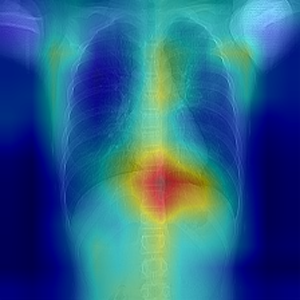

Classify if person has COVID or not and also identifies the regions in lungs it has spread

Built the end-to-end solution. The output also shows why the ML model predicts it is covid positive or negative. Highlights on Xray images are shown and how it resulted in the prediction.